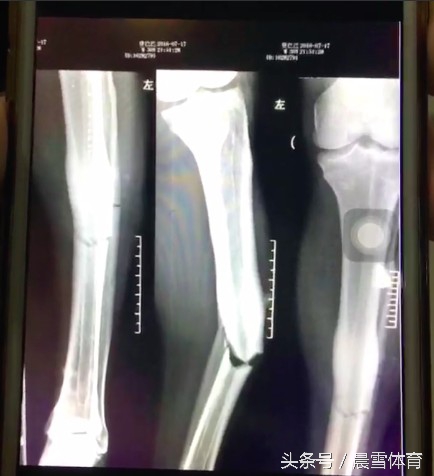

乌兰 在大连大学附属中山医院进行了3个半小时的手术,从X光片来看,乌兰的腓骨明显断裂,他需要3个月的康复时间才能下地走路,1年之后才能拆掉钢板,对他的职业生涯也导致了极大的影响。